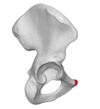

Pubic tubercle

Obturator nerve